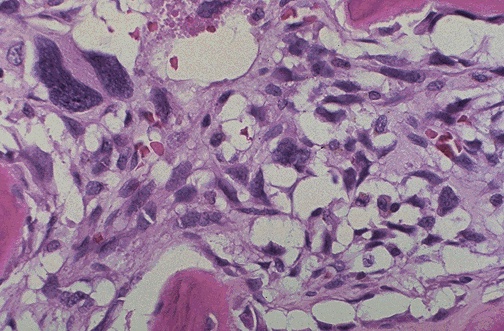

Image 8.4

The high power microscopic appearance of the mass is shown here.